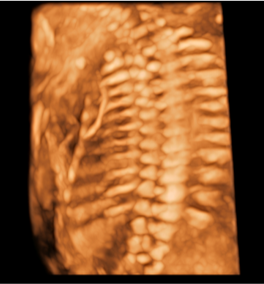

- Skeleton: siêu âm xương thai nhi, phát hiện dị tật xương

Hình ảnh thực tế trên máy siêu âm 5D SonoScape P25